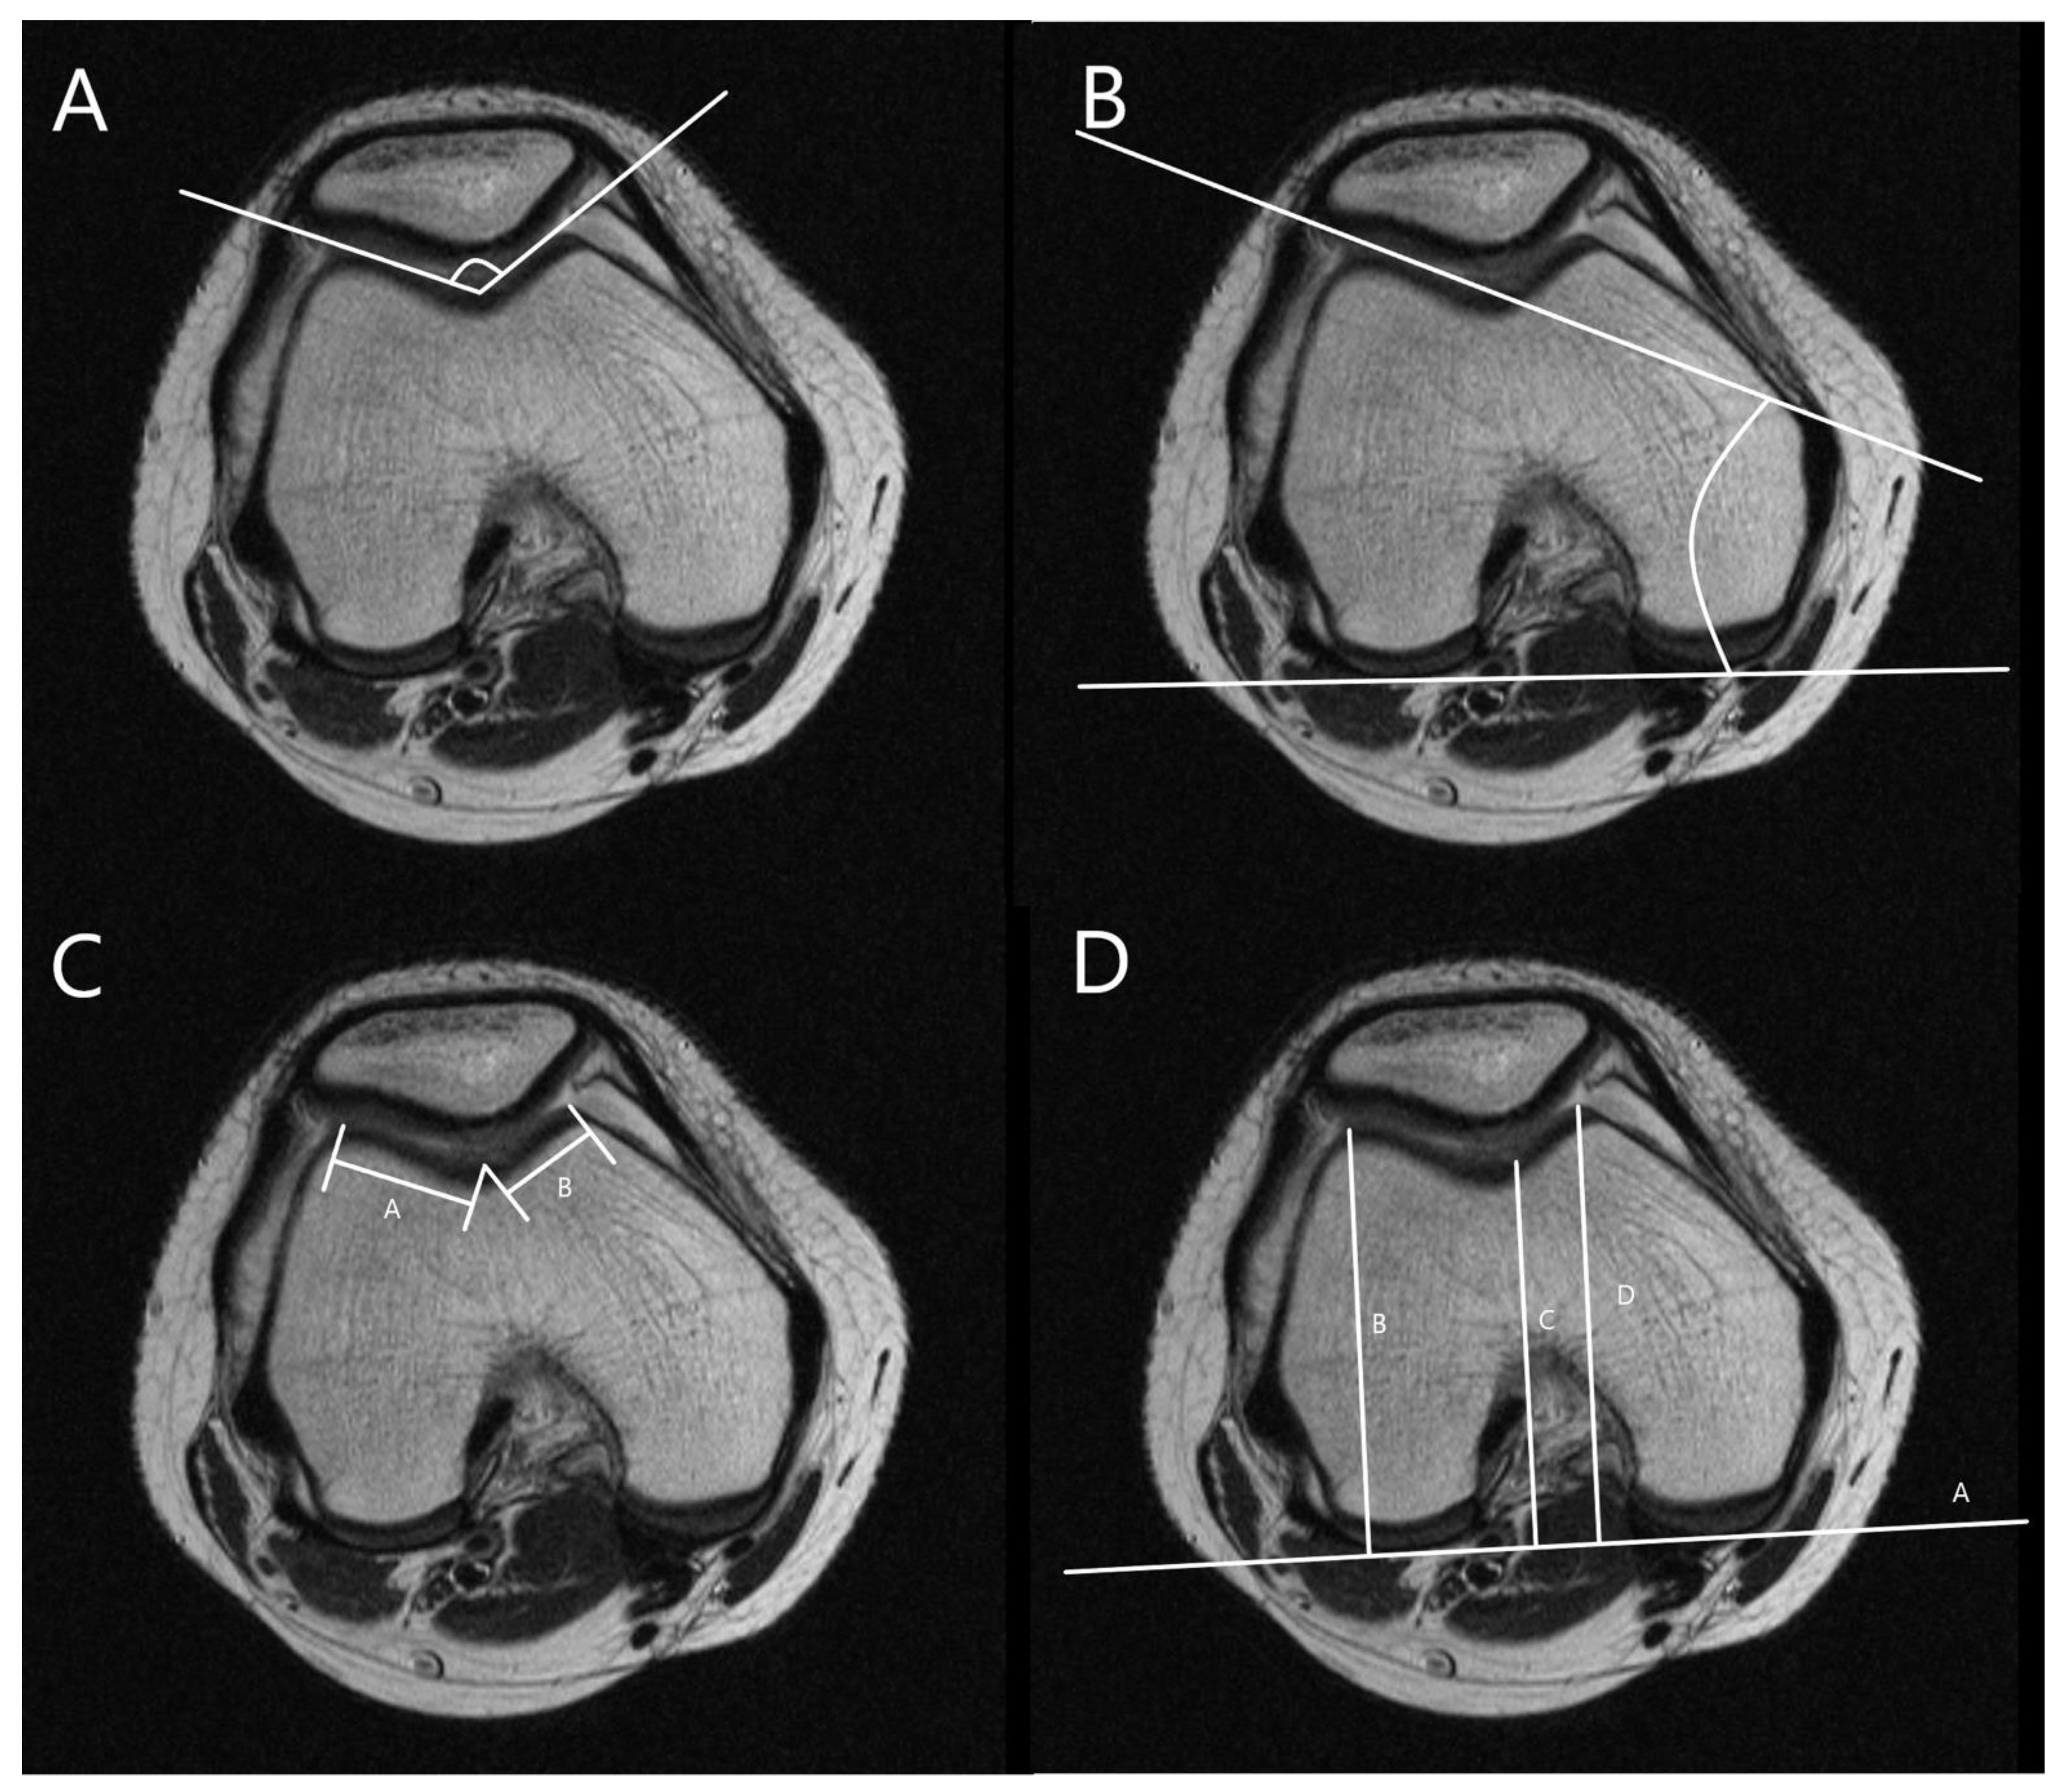

The MRI was performed using a 1.5T (GE Healthcare, Milwaukee, WI, USA). The slice thickness was 3 mm in all sequences. The T1 fat saturation axial imaging was utilized to measure all parameters. The cartilaginous parameters of the patellofemoral morphology including sulcus angle (SA), lateral trochlear inclination (LTI), trochlear facet asymmetry (TFA), and femoral depth (FD) and alignment as well as tibial tuberosity–trochlear groove distance (TT-TG), percent sulcus location (PSL), and percent tibial tuberosity location (PTL) were assessed. Three orthopedic surgeons measured all parameters twice at 8-week intervals using image archiving and communication systems (Maroview, Marotech, Seoul, Korea). The morphological parameters of the patellofemoral joint were measured in the axial slice of MRI, which showed the deepest trochlear groove [18]. SA was defined as the angle between slopes of the medial and lateral trochlea [21,22]. LTI was measured as the angle between a line along with cartilage of lateral trochlear facet and the line along the posterior aspect of the femoral condyle (posterior condylar axis) [21]. TFA was defined as the ratio of the length of the medial trochlear facet to that of the lateral trochlear facet [21,23]. FD was defined as the distance between the deepest point of the trochlear sulcus and posterior condylar axis subtracted from the mean anteroposterior length of medial and lateral femoral condyles (Figure 2) [24].

Figure 2.

Measurements for trochlear morphology. (A) Measurement of sulcus angle (SA), the angle between slopes of the medial and lateral trochlea. (B) Measurement of lateral trochlear inclination (LTI), the angle between a line along with cartilage of lateral trochlear facet and a line along with posterior aspects of femoral condyles (posterior condylar axis). (C) Measurement of trochlear facet symmetry (TFS), the ratio of the length of medial trochlear facet (line B) to that of lateral trochlear facet (line A) [B/A]. (D) Measurement of femoral depth (FD), distance C between the deepest point of the trochlear sulcus and posterior condylar axis subtracted from a mean anteroposterior distance of medial and lateral femoral condyles (lines B and D) [B + D/2 − C].

The alignment parameters of the patellofemoral joint were measured in the axial slice of the deepest trochlear groove and the most prominent tibial tuberosity [25]. The PTL, PSL, and TT-TG were measured as shown in Figure 3 [26,27].

Figure 3.

Position of the trochlear groove and tibial tuberosity. (A) Measurement of percent tibial tuberosity location (PTL). Lines B and C are divided by perpendicular lines from tibial tuberosity to line A [B/A × 100]. (B) Measurement of percent sulcus location (PSL). Lines E and F are divided by perpendicular lines from the deepest portion of the trochlear groove to a line along with posterior aspects of femoral condyles [E/D × 100]. (C) Measurement of tibial tuberosity—trochlear groove (TT-TG) distance, the distance from the deepest point of the trochlear groove to the tibial tuberosity.